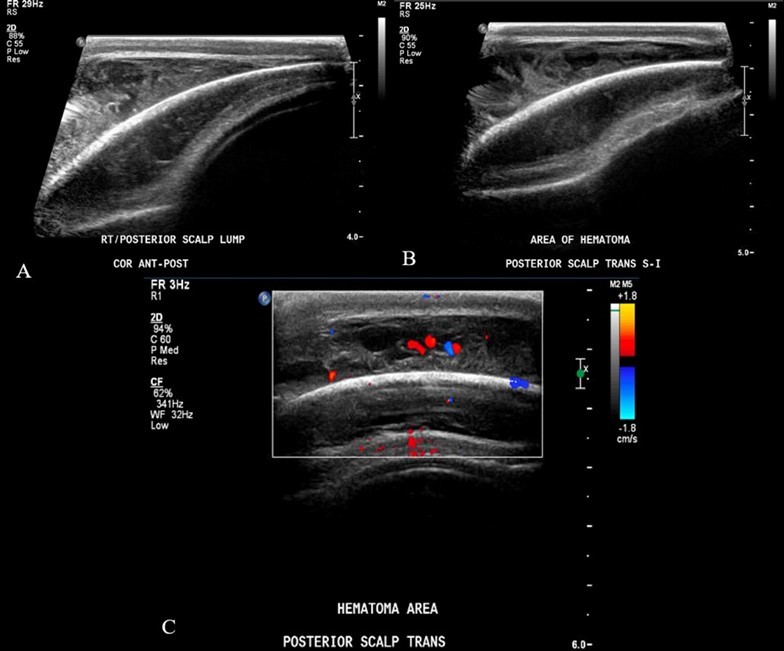

From a musculoskeletal standpoint, MRIs of the cervical, thoracic, and lumbar spine were within normal limits. The patient was started on scheduled acetaminophen for pain management. A CT of the head without contrast showed right high convexity scalp soft tissue swelling without acute intracranial abnormality (Figure 1A – 1F). A complete bone survey was negative for sources of trauma (Figure 2B – 2I) but did note calvarial soft tissue edema (Figure 2A). A head ultrasound confirmed the fluctuance on the patient’s skull to be a subgaleal hemorrhage (Figure 3A – 3C) of 9 mm thickness at its greatest.

Figure 3A – 3C.Ultrasound soft tissue head using multiplanar gray scale and color Doppler images. The superficial subcutaneous soft tissue appears homogeneous and uniform thickness. There is a layer of heterogeneous echogenicity deep to the subcutaneous layer, on the surface of the bone which appears retained by an echogenic capsule or membrane. This measures up to 9 mm greatest thickness. The size of the collection is greater than the transducer can measure. Additional images performed to include the edges of the hemorrhage show uplifting of the galea consistent with subgaleal location. The cranial sutures are not adequately included.